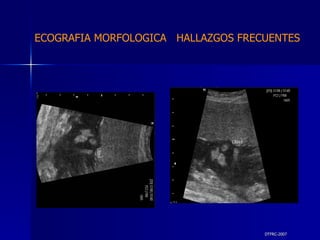

DTFRC-2007 ECOGRAFIA MORFOLOGICA  HALLAZGOS FRECUENTES   GENITOURINARIA DISPLASIA RENAL MULTIQUISTICA  3 HIDRONEFROSIS  2 QUISTE DE OVARIO FETAL  1 SISTEMA DIGESTIVO DILATACION INTESTINAL  2  SISTEMA ESQUELETICO   PIE BOT  2  20 % 6 % 6 %

DTFRC-2007 ECOGRAFIA MORFOLOGICA  HALLAZGOS FRECUENTES   OTROS HIGROMA QUISTICO  2 ENFERMEDAD ADENOMATOSA PULMONAR  1 ARTERIA UMBILICAL UNICA  2 HIDROPS FETAL NO INMUNE  1 QUISTE DE CORDON UMBILICAL  1 ALTERACION DE LIQUIDO ANMIOTICO  2 SINDROME TRAFUSIONAL FETO FETAL 1 LABIO LEPORINO  2 TOTAL  12  42 %